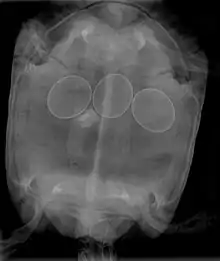

In reptiles

In reptiles, it is inadvisable to attempt to break a reptile egg to remove it from an egg-bound female. This procedure may be done by a veterinarian, who will insert a needle into the egg, and withdraw the contents with a syringe, allowing the egg to collapse and be removed. Non-surgical interventions include administering oxytocin to improve contractions and allow the egg(s) to pass normally. In many cases, egg-bound reptiles must undergo surgery to have stuck eggs removed.

Egg binding in reptiles is quickly fatal if left untreated; therefore, gravid females who become very lethargic and cease feeding need immediate medical treatment in order to treat the potentially life-threatening condition.

Egg binding can occur if an egg is malformed and/or too large, the animal is weakened by illness, improper husbandry, stress, or if hormonal balances are wrong (producing weak contractions). Factors that can contribute to the risk of egg binding include calcium deficiency, breeding animals that are too young or too small, not providing suitable laying areas (leading to deliberate retention of eggs), and overfeeding of species in which clutch size is dependent on food intake, such as the Veiled Chameleon.